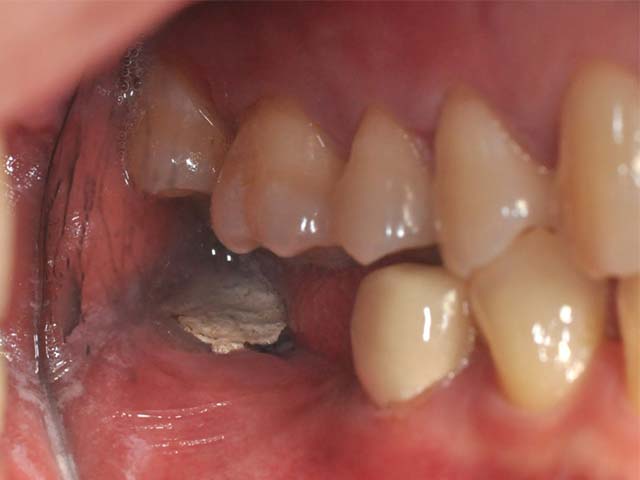

牙橋嚴重蛀牙,即拔即種,避免二次傷口 首頁 案例分享 人工植牙 牙橋嚴重蛀牙,即拔即種,避免二次傷口 多年前製作之牙橋,因為二度齲齒,導致支台齒蛀蝕,而需重新製作 牙橋支臺齒嚴重蛀牙 STEP1.拔除殘根並植入兩根植牙 STEP2.骨粉填補缺損骨頭缺陷 STEP3.三個月後,準備製作正式假牙 STEP4.正式假牙完成